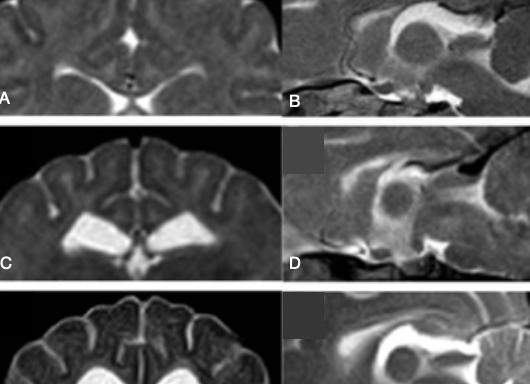

В случае аплазии (агенезии) и гипоплазии мозолистого тела основная спайка, образованная комиссуральными волокнами или частично, или полностью отсутствует и третий желудочек остается открытым. При агенезии имеются столбы свода и прозрачные перегородки, а в случае гипоплазии наблюдается отсутствие лишь задней спайки, а мозолистое тело укорочено. Пороки в мозолистом теле в основном сопровождают и иные нарушения в головном мозге, хотя могут иметь место и изолированно.

Данная патология может иметь разную степень структурного проявления и выражаться в виде тотального отсутствия, частичного (гипогенез) либо неправильного (дисгенезия) формирования, недоразвития (гипоплазия) мозолистого тела.

Вместо нормальной структуры, которая выглядит как широкая плоская полоса, большая спайка приобретает вид укороченных перегородок или прозрачных столбов свода.

В качестве основного метода используют метод эхографии, находят применение также процедуры МРТ, УЗИ.